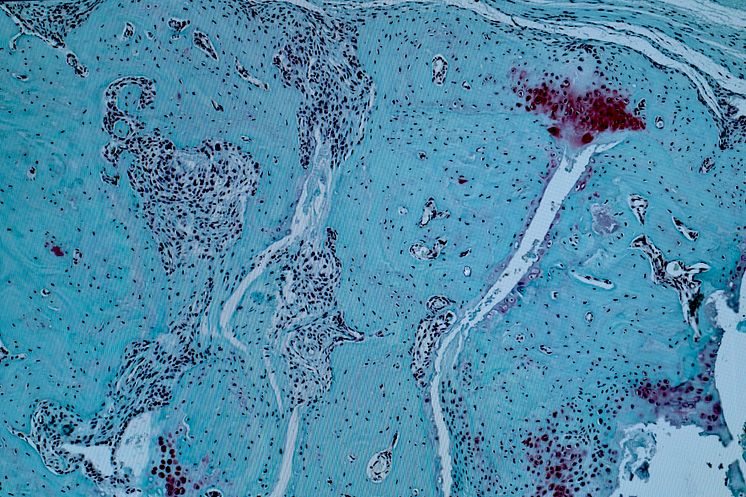

Mikroskopbild av vävnadsprov som visar kraftig brosk- och ledförstörelse p g a ledgångsreumatism.